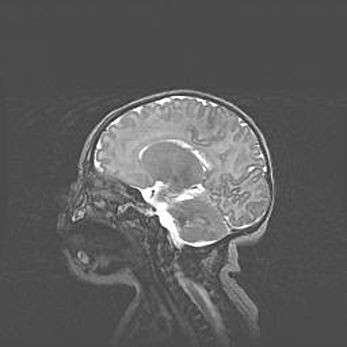

Ниже представлена  галерея МРТ снимков, полученных с применением LMT неонатальных матричных РЧ катушек. Также каждая группа МРТ снимков сопровождается информацией о пациенте (диагноз, возраст, вес, пол, срок гестации) и краткой сопроводительной расшифровкой диагноза.

Церебральная ишемия II.

Возраст: 5 дней

Вес: 3400 г

Пол: женский

Окружность головы: 35 см

Срок гестации: 39 недель

Церебральная ишемия – это заболевание, характеризующееся недостаточностью (гипоксией) либо полным прекращением (аноксией) снабжения мозга кислородом по причине закупорки одного или нескольких сосудов. Это приводит к  что метаболическим расстройствам различной степени тяжести в тканях головного мозга, развитию коагуляционных некрозов и гибели нейронов.